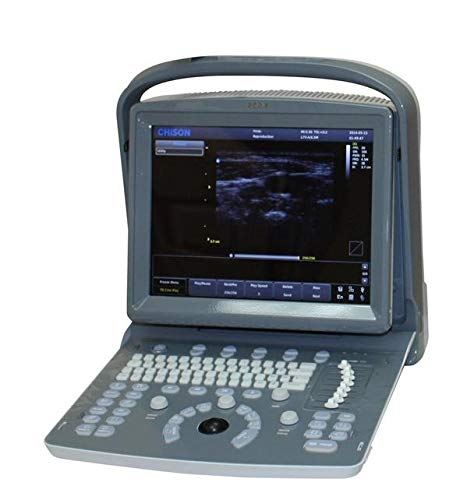

DIAGNOSTIC ULTRASOUND MACHINES FOR SALE